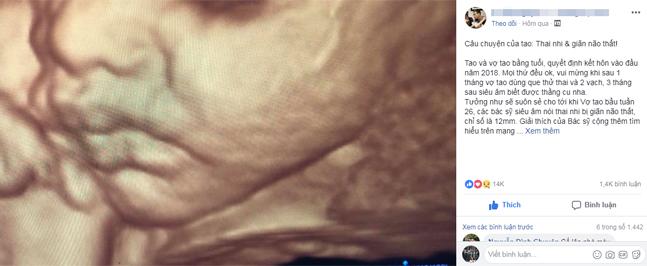

Kết quả siêu âm thai nhi bị giãn não thất, chỉ số là 12mm khi thai nhi ở tuần 26 đã khiến vợ chồng anh Lê Hải Nguyên không thể trụ nổi.

3 tháng sau, anh chị hạnh phúc hơn khi bác sĩ thông báo con giống bố. Mọi việc cứ diễn ra êm đềm trong niềm hạnh phúc của anh chị. Là con đầu nên anh chị dành hết tình yêu thương, sự chăm sóc cho con với mong muốn con chào đời khỏe mạnh. Thế nhưng, những ngày “sóng yên biển lặng” ấy lại báo hiệu một cơn bão sắp đến với vợ chồng anh khi thai ở tuần 26 đi siêu âm hay tin thai nhi bị giãn não thất, chỉ số là 12mm.

“Giải thích của bác sĩ cộng với việc tìm hiểu thêm trên mạng, mình hiểu bé nằm ở mức 10-15mm, là mức nhẹ có % sinh ra các dị tật. Mức nặng là >15mm tức là não úng thủy, mức nặng này với dị tật là bác sĩ sẽ khuyên dừng thai”, anh Nguyên cho hay.

Được sự hướng dẫn của bác sĩ, vợ chồng anh ra Hà Nội, đến Trung tâm chẩn đoán trước sinh của Bệnh viện Phụ Sản TW để siêu âm hội chẩn với hy vọng kết quả trước đó là không đúng. Thế nhưng, anh chị vẫn nhận kết quả như vậy, giãn não thất, chỉ số 12mm. Tại đây, anh chị được bác sĩ khuyên nên chọc ối để xét nghiệm kiểm tra nhiễm sắc thể (NST) xem có phải là nguyên nhân gây nên giãn não thất không.